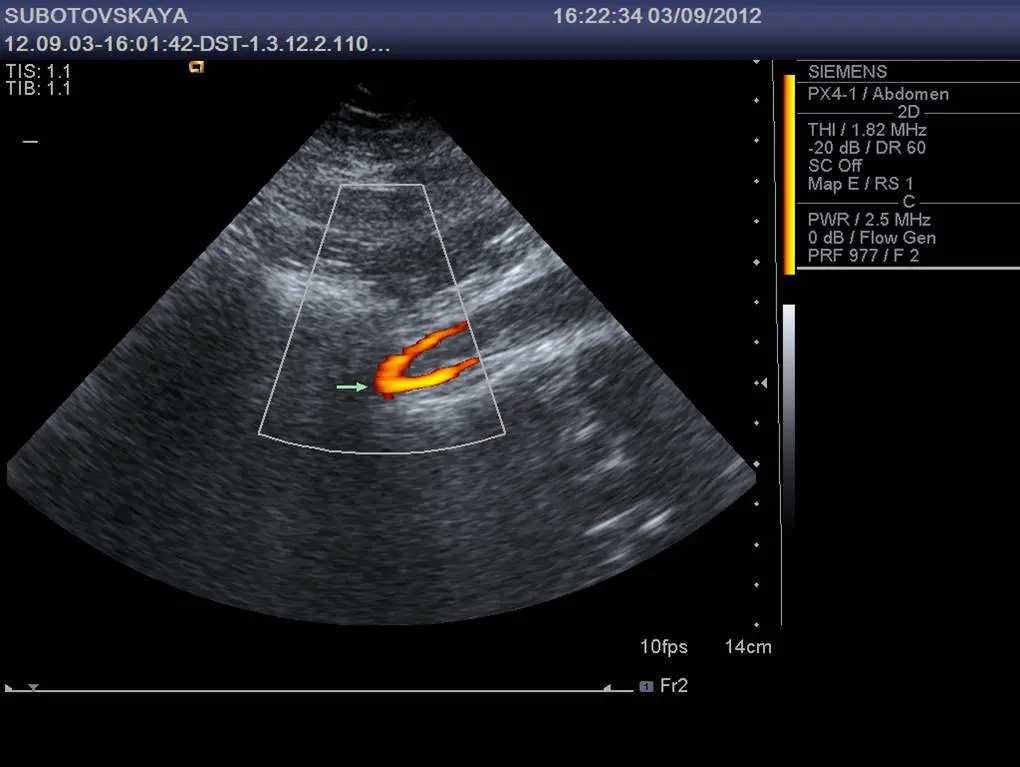

Дуплексне сканування (УЗД) судин нижніх кінцівок за своєю інформативності, безпеки і якості отримуваної інформації по праву вважається золотим стандартом діагностики даних захворювань.

Метод дозволяє максимально об’єктивізувати картину захворювання: можна виміряти діаметри розширених судин, оцінити їх прохідність, варіанти анатомічної будови, роботу клапанного апарату судин (всередині судин є клапани – перегородки, необхідні для того, щоб кров по судинах могла підніматися знизу вгору, при прогресуванні варикозного розширення судин, клапани перестають нормально працювати).

При плануванні операції на судинах, ми маркером на ногах відзначаємо розташування перфорантних судин (це такі вени-містки, які з’єднують поверхневі і глибокі судини між собою, якщо ці судини не прибрати під час операції, то велика ймовірність рецидиву – повторного розширення поверхневих судин).

Також метод цінний тим , що дозволяє бачити зміни не тільки в судинах, але і в навколишніх тканинах: розриви м’язів, гематоми, пухлини, які можуть мати ідентичну клінічну картину з тромбозом глибоких судин (всі вони супроводжуються набряком гомілок з болем в литкових м’язах, тому нерідко доводиться стикатися з ситуацією, коли людину без проведення якісної ультразвукової діагностики лікують від тромбозу глибоких судин, хоча він цієї патології не має).